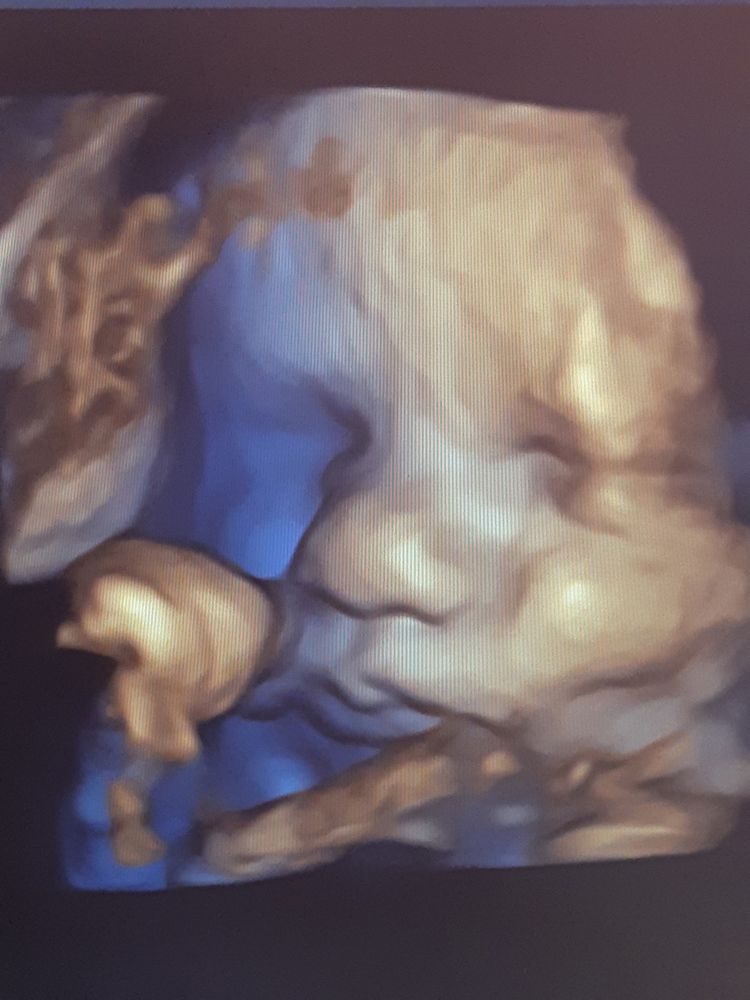

УЗИ 34н+2д. Дилемма со сроком, когда идти в следующий раз?

О практически как мой. Мы вчера ровно в 34 были 2550. У нас только бедро 66, а у вас 69. С так голова тоже 328 и животик 308👌. Я в 36 ровно опять на узи, но я из-за резуса хожу часто, ну и рубец совсем тонкий 1.1мм.

НЮША (ник в ИГ Visla79), Растут парнишки вровень))) Вам тоже ставят больше срок? Или это от аппарата как то зависит? У меня резус тоже отрицательный, но нет антител, поэтому не мониторю на постоянной основе, а вот перед родами хотелось бы точнее знать как дела обстоят. Почитала Ваш пост, уже и дату встречи примерно назначили, эх так волнительно, когда известно заранее)